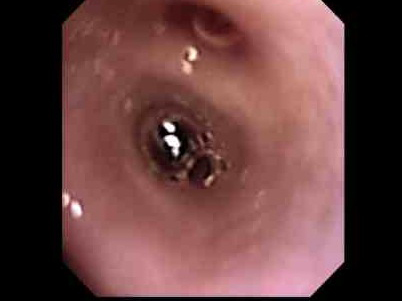

慢性的にくしゃみ、鼻水がでているわんちゃんの鼻腔内観察および生検を行いました。

口から内視鏡をいれ、咽頭部、鼻腔内と進めていきます。

病変部です。血液の混じった粘性のある鼻汁。粘膜には炎症所見が確認できます。

この子は生検により鼻から出血しないよう、滅菌ブラシにて生検を行ないました。